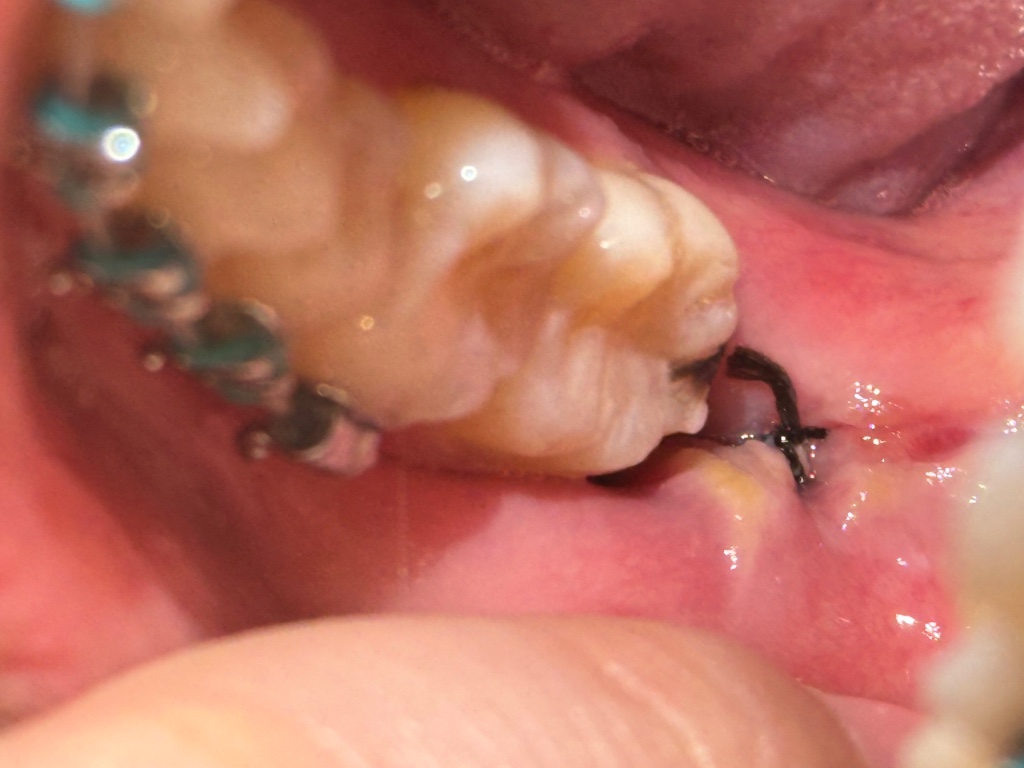

ผ่าฟันคุดได้4วันแล้วมีกิ่นปากแรงมากกับแผลแบบนี้ปกติมั้ยค่ะแล้วเราไม่ได้กินยาฆ่าเชื้อตามหมอสั่งด้วยจะเป็นอาไรมั้ย

ผ่าฟันคุด 4 วัน แบบนี้ปกติไหมคะ

ผ่านมา 4 วัน ต้องคาฟันไม่ให้วางทับกัน วันนี้ต้องวางสูงขึ้นกว่าวันอื่น ๆ ไม่รู้ว่าเพราะบวมขึ้นไหม // แผลดูปกติไหมคะ ที่วงกลมนั่นคืออะไร เพิ่งขึ้นมาวันนี้เลยค่ะ 🥹